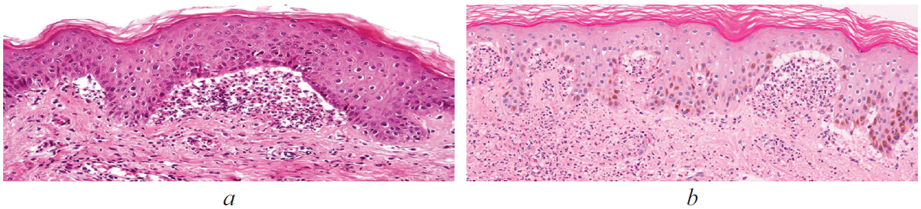

В данной статье представлен случай клинического наблюдения ребенка 5 лет с герпетиформным дерматитом Дюринга. Этот редкий дерматоз характеризуется хроническим рецидивирующим течением, наличием зудящих полиморфных высыпаний, типичными гистологическими и иммуноморфологическими признаками. Диагноз был выставлен на основании клинической картины, данных гистологического и иммуногистохимического исследования биоптата кожи, а также данных результатов исследования HLA-типирования методом ПЦР. Клиническое наблюдение этого случая представляет интерес для практикующих врачей-дерматологов в связи с редкой встречаемостью герпетиформного дерматита Дюринга у детей, сложностью дифференциально-диагностического поиска, что требует дальнейшего обобщения опыта с применением гистологических, иммуногистохимических и молекулярно-генетических методов исследования. Герпетиформный дерматит представляет собой хронические интенсивно зудящие папуло-везикулезные высыпания, которые, как правило, имеют симметричную локализацию на разгибательных поверхностях конечностей. Заболевание четко дифференцируется от других высыпаний с образованием субэпидермальных пузырей по гистологическим, иммунологическим и гастроинтестинальным критериям. Распространенность дерматоза в различных популяциях европиоидной расы составляет от 10 до 39 случаев на 100 000 населения. Герпетиформный дерматит Дюринга может развиться в любом возрасте (зарегистрированы случаи детской формы герпетиформного дерматита Дюринга), однако чаще всего заболевание встречается в возрасте 40–50 лет. Герпетиформный дерматит персистирует неопределенно долго с переменной степенью тяжести. У пациентов с дерматитом Дюринга нередко отмечается ассоциированная глютен-чувствительная энтеропатия, в большинстве случаев протекающая бессимптомно.